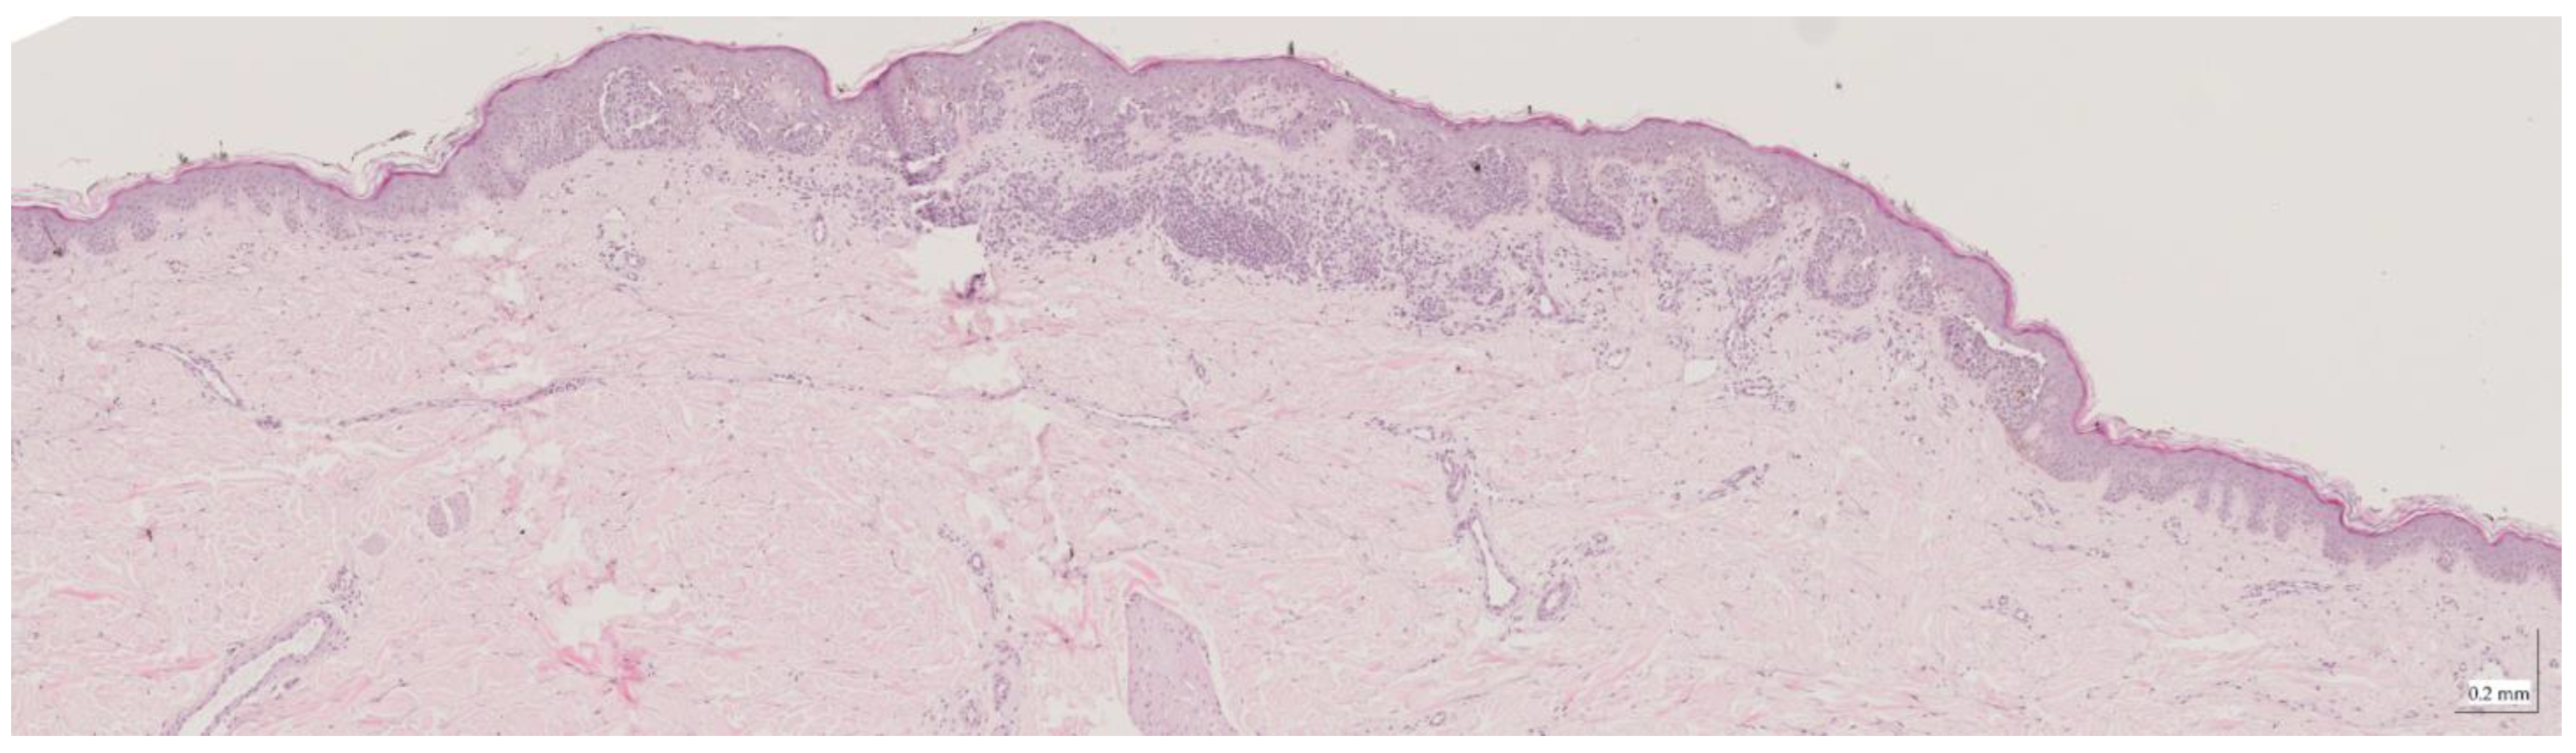

Appendix A. Selected Cases Studies’ HE Histopathological Images (Limited to OCT FOV)

| Compound nevus (CN) Case 2 | Localization: right posterior thigh |

![]() | ![]() |